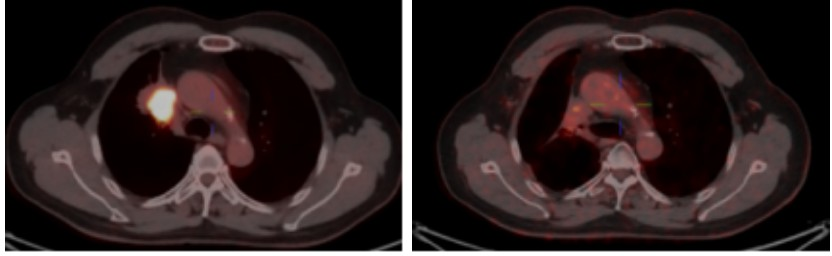

Figure 5. Comparison of the primary pulmonary lesions on PET/CT before and 2 years after heavy ion therapy